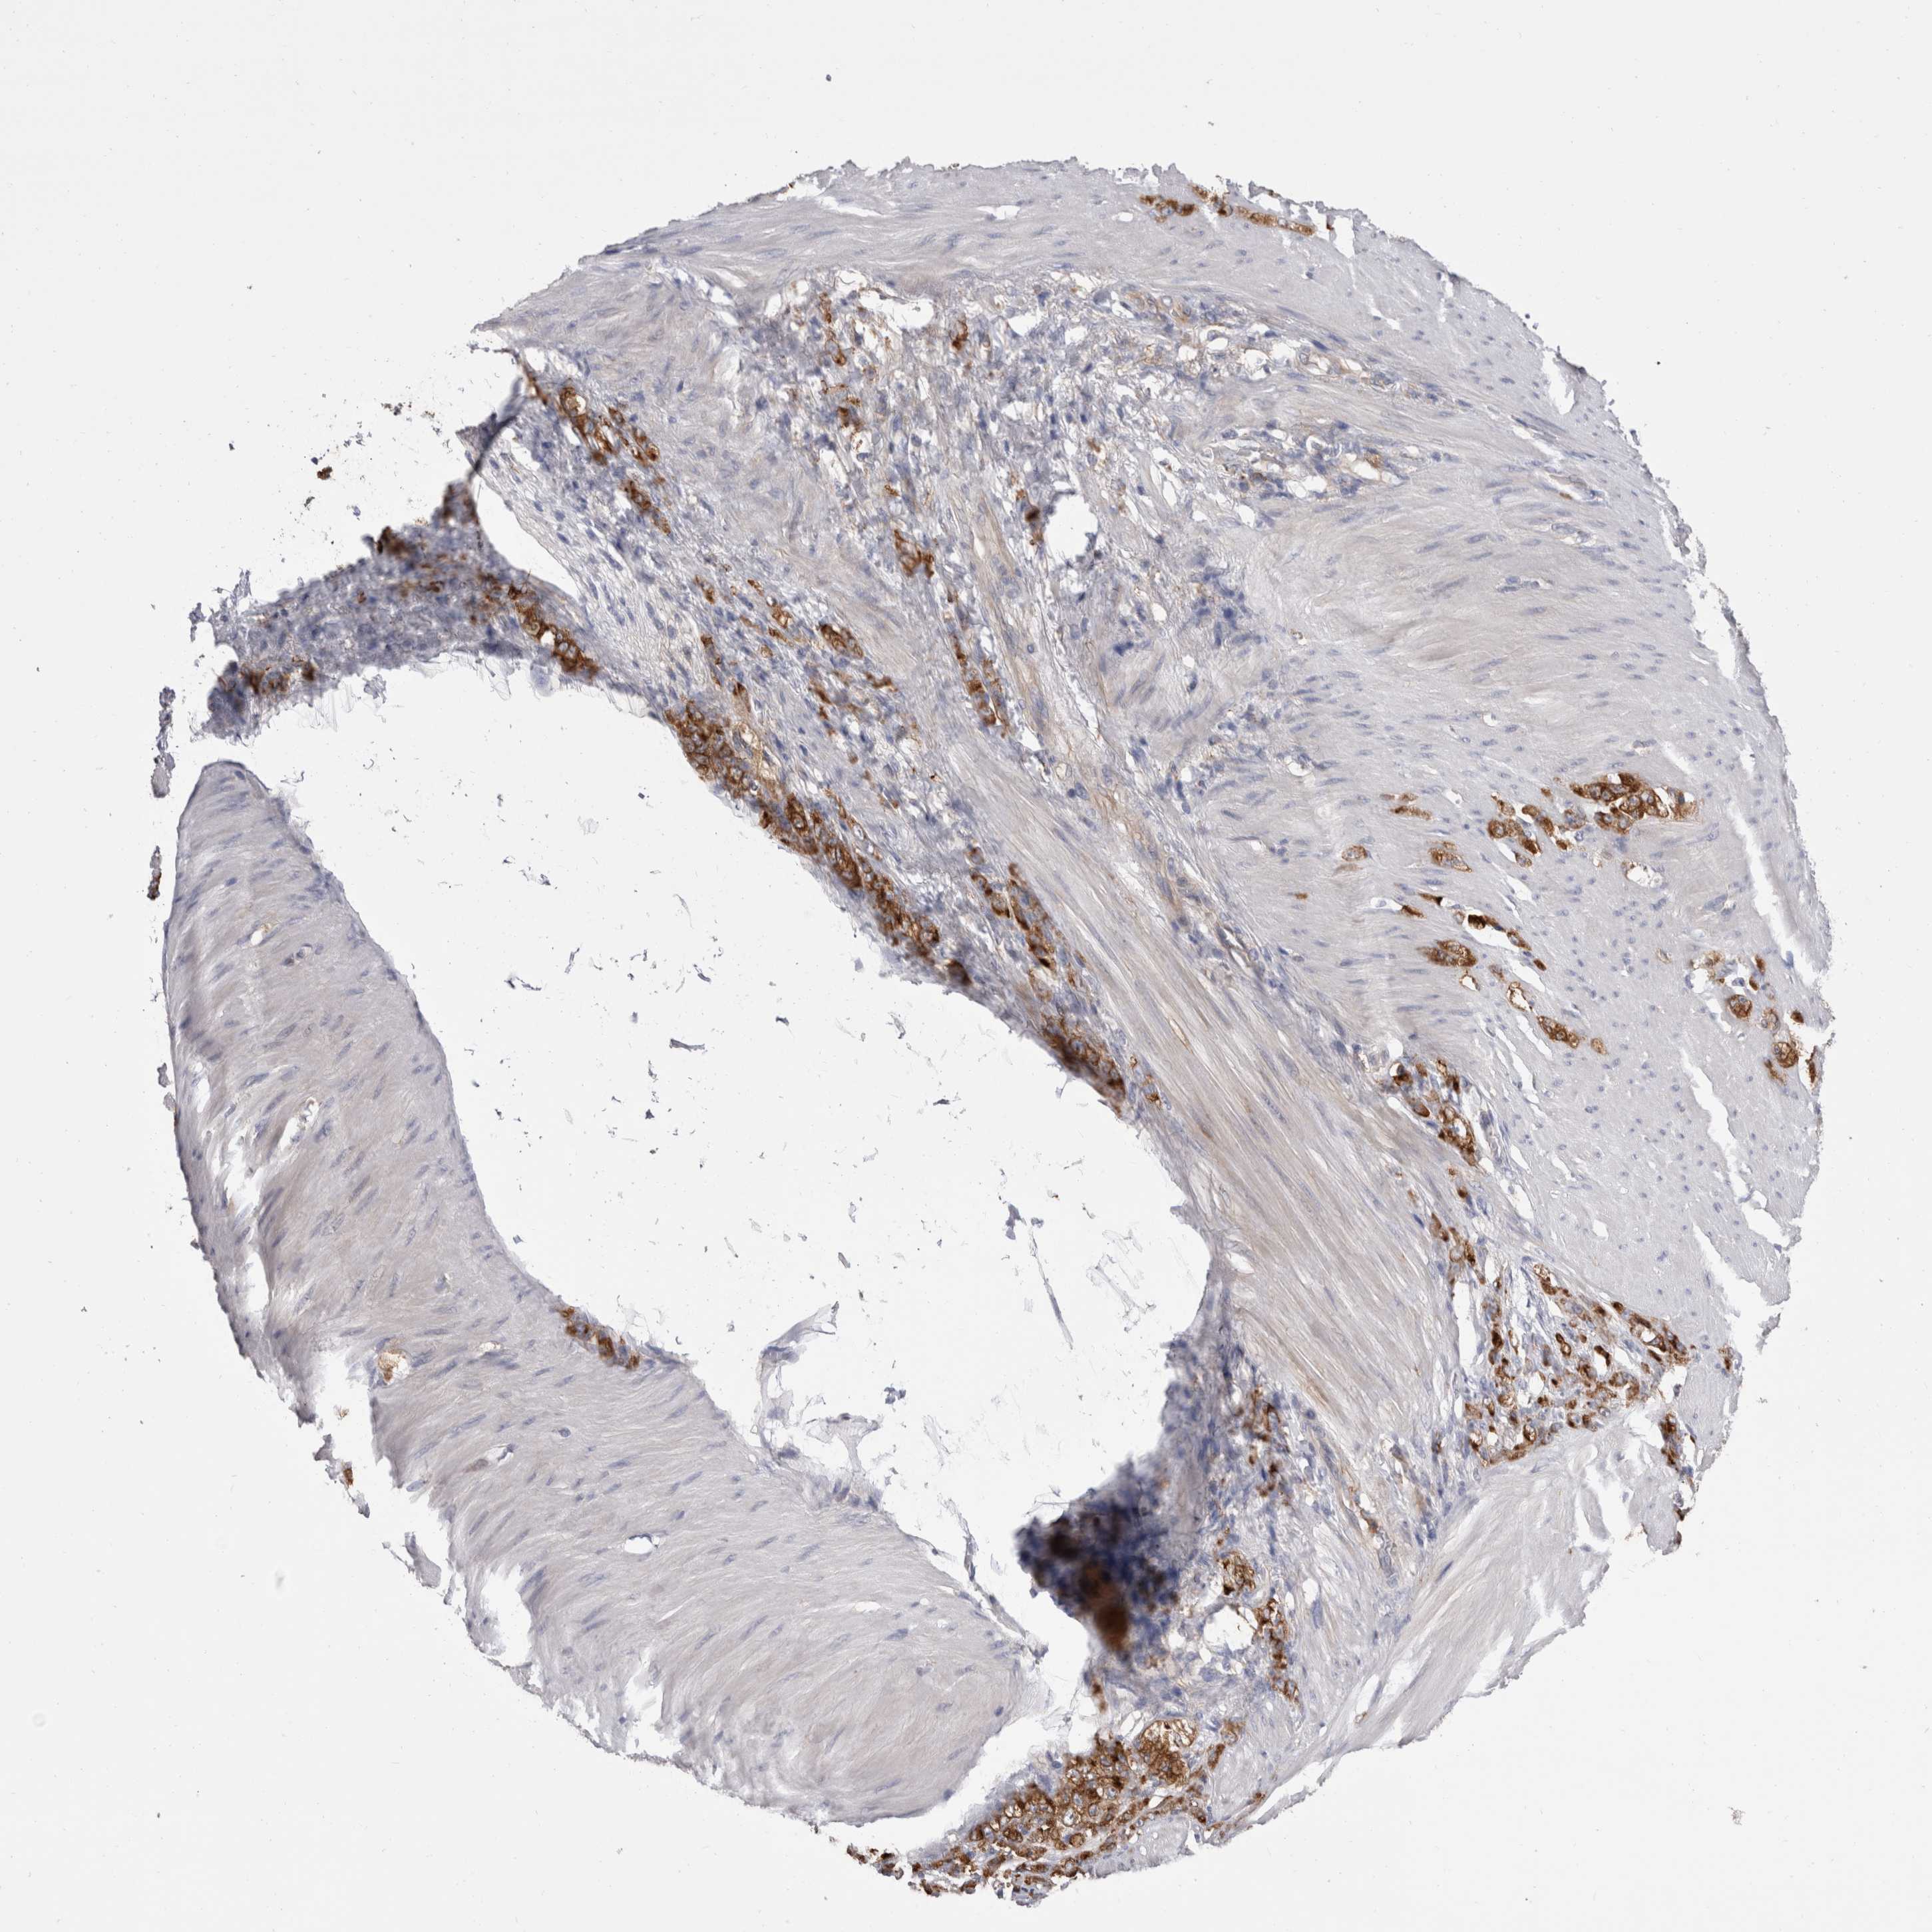

STOMACH CANCER - Protein expressioni

A mouse-over function shows sample information and annotation data. Click on an image to view it in a full screen mode. Samples can be filtered based on level of antibody staining by selecting one or several of the following categories: high, medium, low and not detected. The assay and annotation is described here.

Note that samples used for immunohistochemistry by the Human Protein Atlas do not correspond to samples in the TCGA dataset.

Antibody stainingi

Antibody staining in the annotated cell types in the current human tissue is reported as not detected, low, medium, or high, based on conventional immunohistochemistry profiling in selected tissues. This score is based on the combination of the staining intensity and fraction of stained cells.

Each image is clickable and will lead to virtual microscopy that enables deeper exploration of all samples and also displays staining intensity scores, fraction scores and subcellular localization as well as patient and tissue information for each sample.

Antibody HPA023904

Antibody HPA024010

Antibody HPA025960

Antibody CAB017037

Staining

High

Medium

Low

Not detected

Intensity

Strong

Moderate

Weak

Negative

Quantity

>75%

75%-25%

<25%

None

Location

Nuclear

Cytoplasmic/membranous

Cytoplasmic/membranous,nuclear

Adenocarcinoma, NOS